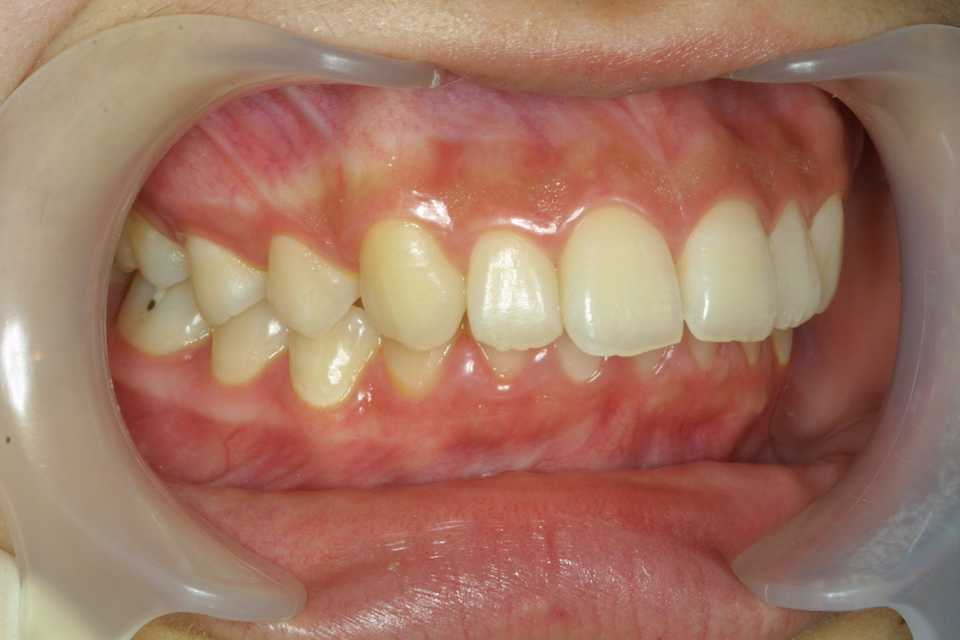

16歳女子、下顎後退位、両側性顎関節症で口が開かなくなって、近所の歯医者をハシゴしたが治らずうちに来た。ディープバイトというのは時折見かけるが、下顎が後方に変移していて、顎関節に負担がかかりやすい噛み合わせだ。少し前の方で噛める噛み合わせにしてあげると治る。見かけも同時に治る。では時系列でどうぞディープバイトは下の前歯が上の歯に隠れて見えない程に噛み合わせが深いということだ。下顎が後方に行き過ぎていることがほとんどなので、ちょっと前で噛めるようにしてあげると改善する。その噛み合わせの位置だと臼歯部に隙間ができるので、それを埋めるような歯列矯正をすれば良い。下顎の3、4間に上下的な段差があるので、ワイヤーが一直線に並べば良い。一直線に並ぶどころか、臼歯部をさらに揚げている。1年1ヶ月後治ったのでブラケットを外した。新しい噛み合わせに慣れたことを確認する。デュアルバイト(元の位置でも噛める)にならないように注意する。1年5ヶ月後3年後、まあまあ安定している。